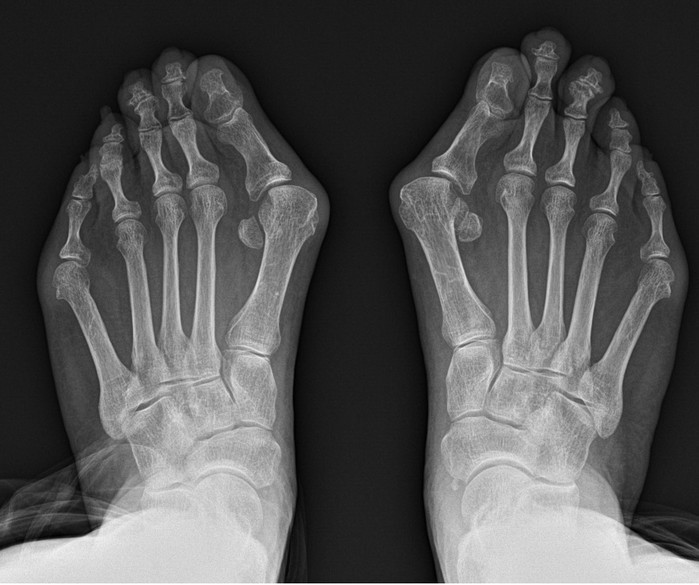

그 대표적인 예로 무지외반증을 꼽을 수 있다. 무지외반증 이란 엄지발가락이 새끼발가락 방향으로 휘며 엄지발가락이 시작되는 관절의 뼈가 돌출되는 질환이다.

무지외반증을 포함한 족부 질환 치료에 오랜 기간 매진해온 연세건우병원 박의현 병원장(정형외과 전문의)은 “무지외반증은 필연적으로 보행의 불균형을 유발한다. 정상인은 보행 시 엄지발가락에 체중의 약 60%가 실리지만 무지외반증 환자는 엄지발가락이 휘어져 있어서 그 반대로 발의 중지나 약지에 몸무게가 쏠려 정상적인 보행이 불가능해진다”고 설명한다.

이에 무지외반증 환자는 무의식적으로 엄지발가락에 체중을 싣지 않고 걷게 돼 필연적으로 발목·무릎·허리에 불필요한 스트레스가 발생, 관절·척추 질환으로 이어질 수 있다. 실제 여성 무릎관절염 환자 중 무지외반증이 동반은 비교적 흔한 편이다.

그래서 무지외반증은 되도록 빨리 치료하면 좋지만 실제로 보행에 큰 지장이 오기 전까지는 방치하는 경우가 대다수다. 오랜기간 방치하게 되면 수술이 필요하게 되는데, 발은 여러 뼈가 얽혀있는 생각보다 복잡한 부위다. 그래서 환자들은 과연 수술 후 발 모양이 정상으로 돌아올지 그리고 통증은 심하지 않은지 걱정하게 된다.